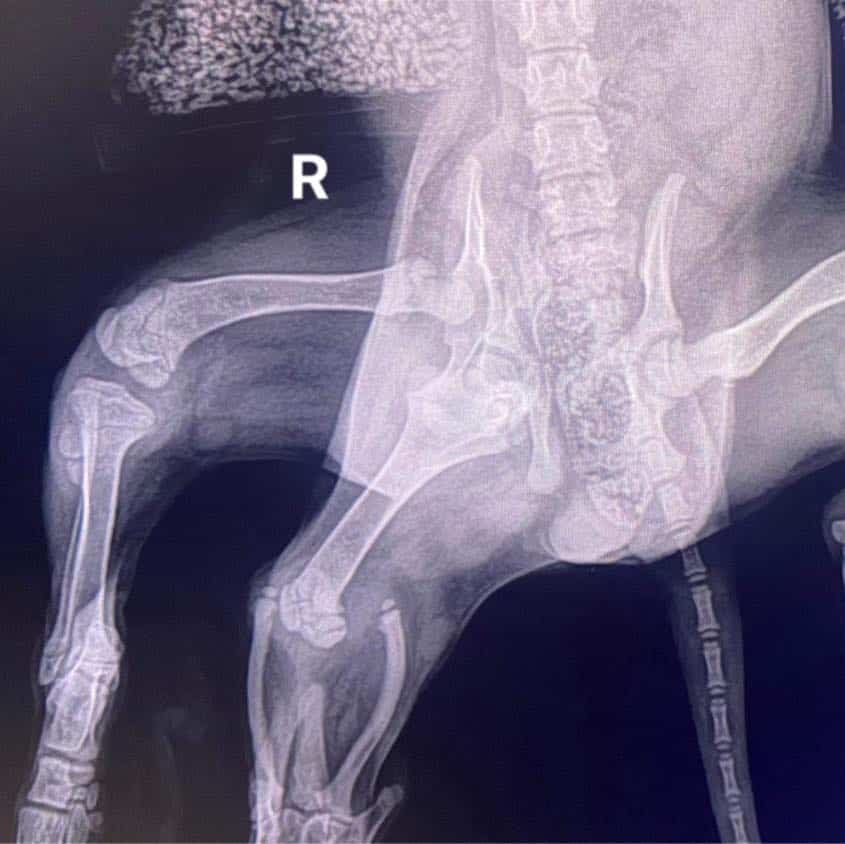

Despite her physical differences—additional back legs and an incomplete pelvis due to an extra hip joint—the shelter was optimistic. They planned to let her settle before considering surgical options to remove the unnecessary limbs and assess the functionality of her remaining leg.

After a period of rest and numerous vet visits, Arie was ready for surgery. The procedure was successful. As surgeon Aaron Lutchman told the BBC, “She’s doing really well, she’s bounced back and she’s a happy little dog.” Ariel was soon up and exploring, thanks to her dedicated foster family, who ensured her recovery went smoothly.